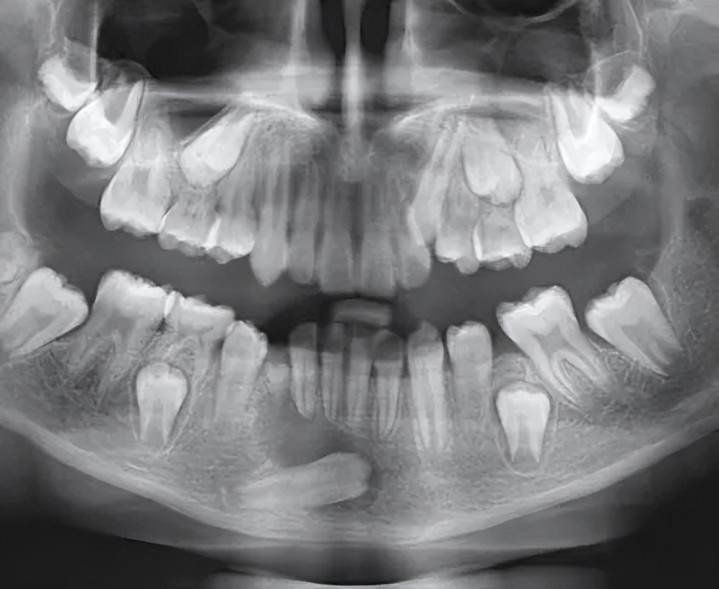

换牙期,恒牙如故“破土而出”,对应的乳齿却迟迟不掉,占了位置。这种“钉子户”乳齿必须实时拔掉,给恒牙闪开。